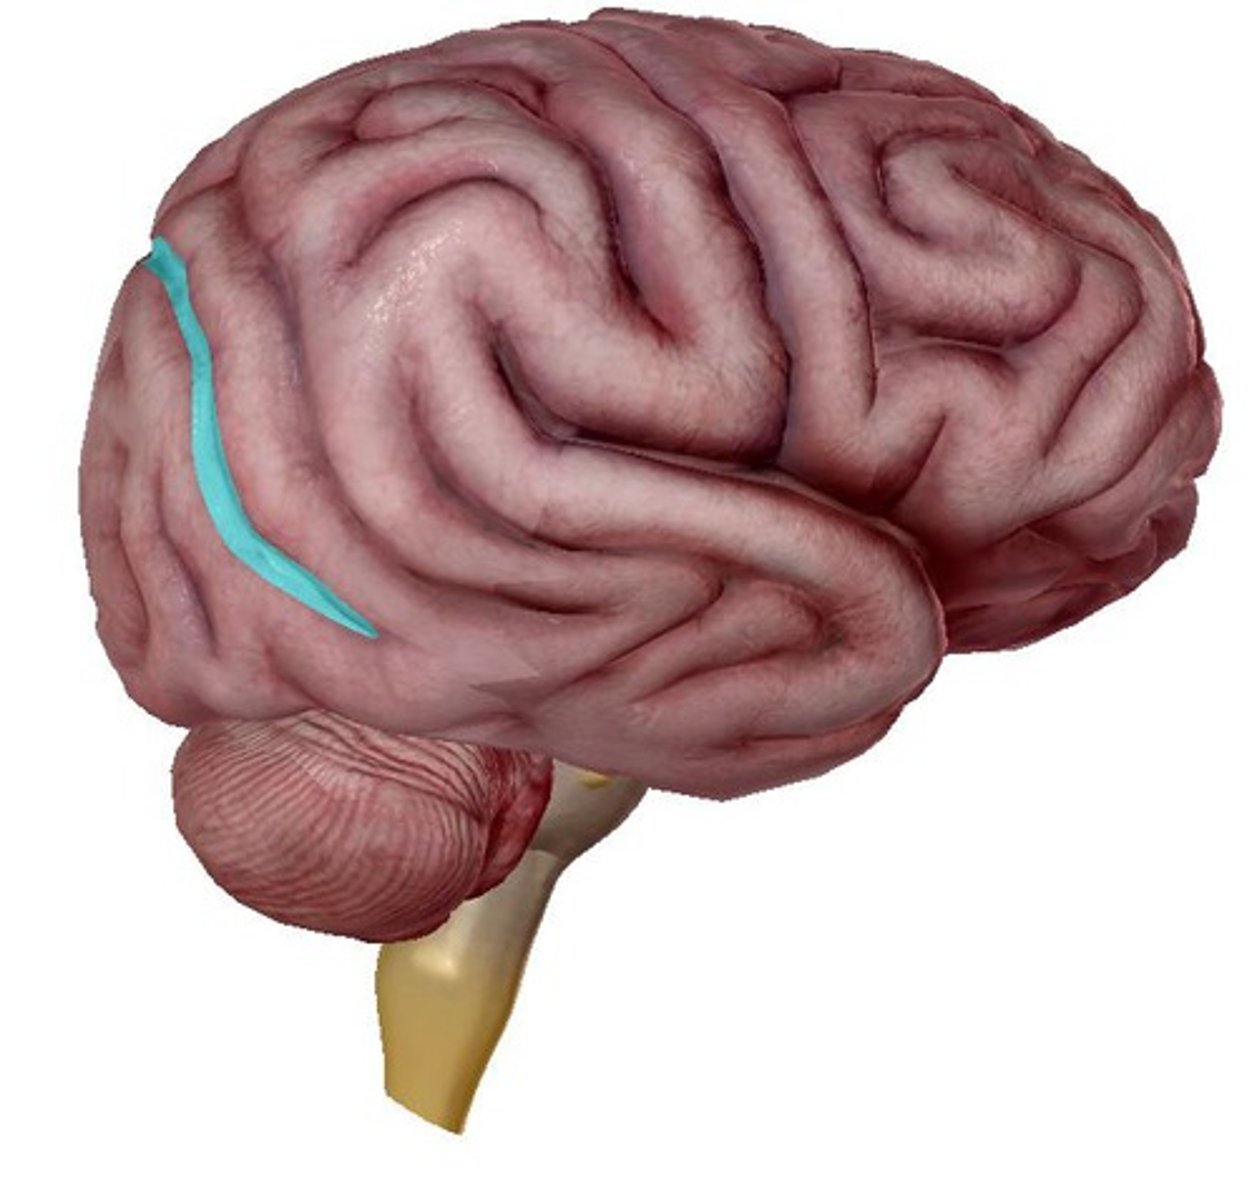

Lateral sulcus

depression